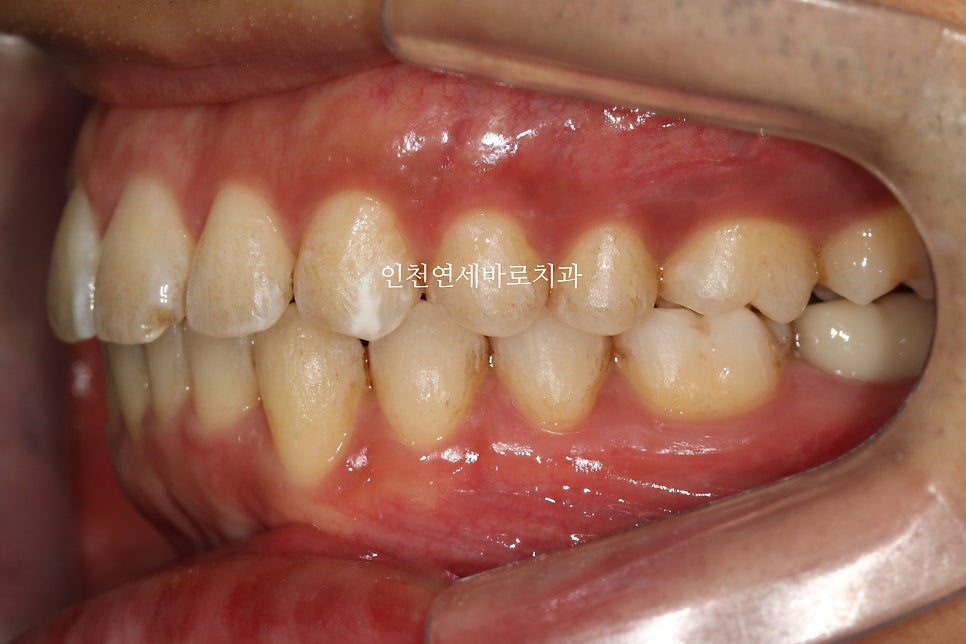

앞니가 뻗쳐있고, 아래치아가 안보이고

덧니가 심해서 내원한 환자분입니다

치료 전과 후의 비교입니다.

교합도 양호하게 마무리.

악궁의 확장을 통한 앞니의 후방이동도 최대한 이루어냈습니다.